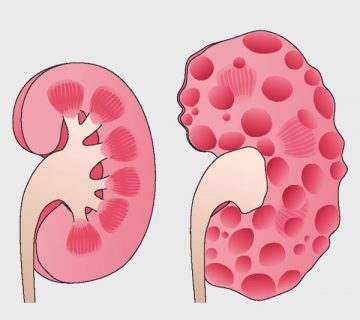

مطالب آموزشی در زمینه های مشاوره ژنتیک اصفهان ، آزمایش ژنتیک اصفهان ، بهترین آزمایشگاه ژنتیک اصفهان ، بیماری های ژنتیکی ، آزمایشات ژنتیک ، تست های ژنتیک، غربالگری ، نازایی ، سقط های مکرر ، مشکلات و اختلالات ژنتیکی ، ازدواج های فامیلی و .. قرارداده میشود.